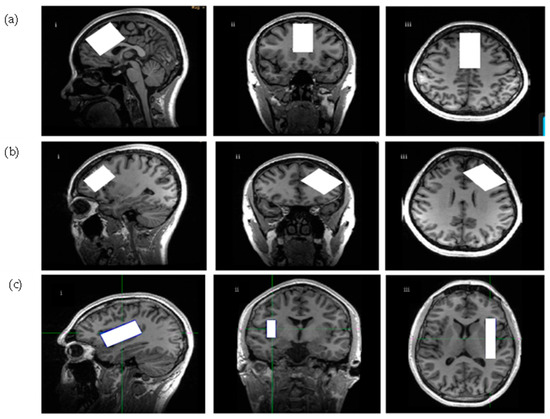

4.4.1. Scanning Procedures

4.4.2. Spectroscopic Parameters